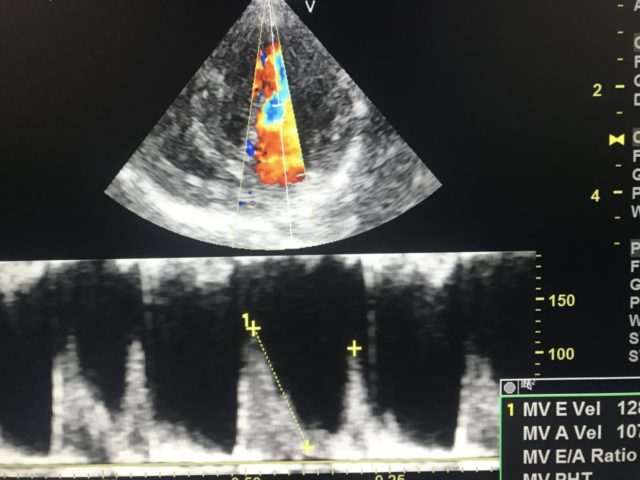

胸部エコーでは心臓の内部の構造の変化、例えば心臓の筋肉の肥大、心房、心室の拡大、心臓弁の変化などが確認出来ます。

更に今回の胸部エコーではカラードプラ、連続波ドプラ機能を利用して心臓内の血流速度を測定できるようになりました。

【血液の逆流を測定】

耳では聞こえないような逆流も画像ではハッキリと描出できます。

【血液の逆流をカラードプラ法で描出】

また血流速度を測定して数字に表すことによって、病態の進行度を推測して経時的観察することも可能です。

【左心室への血液流入速度の測定】